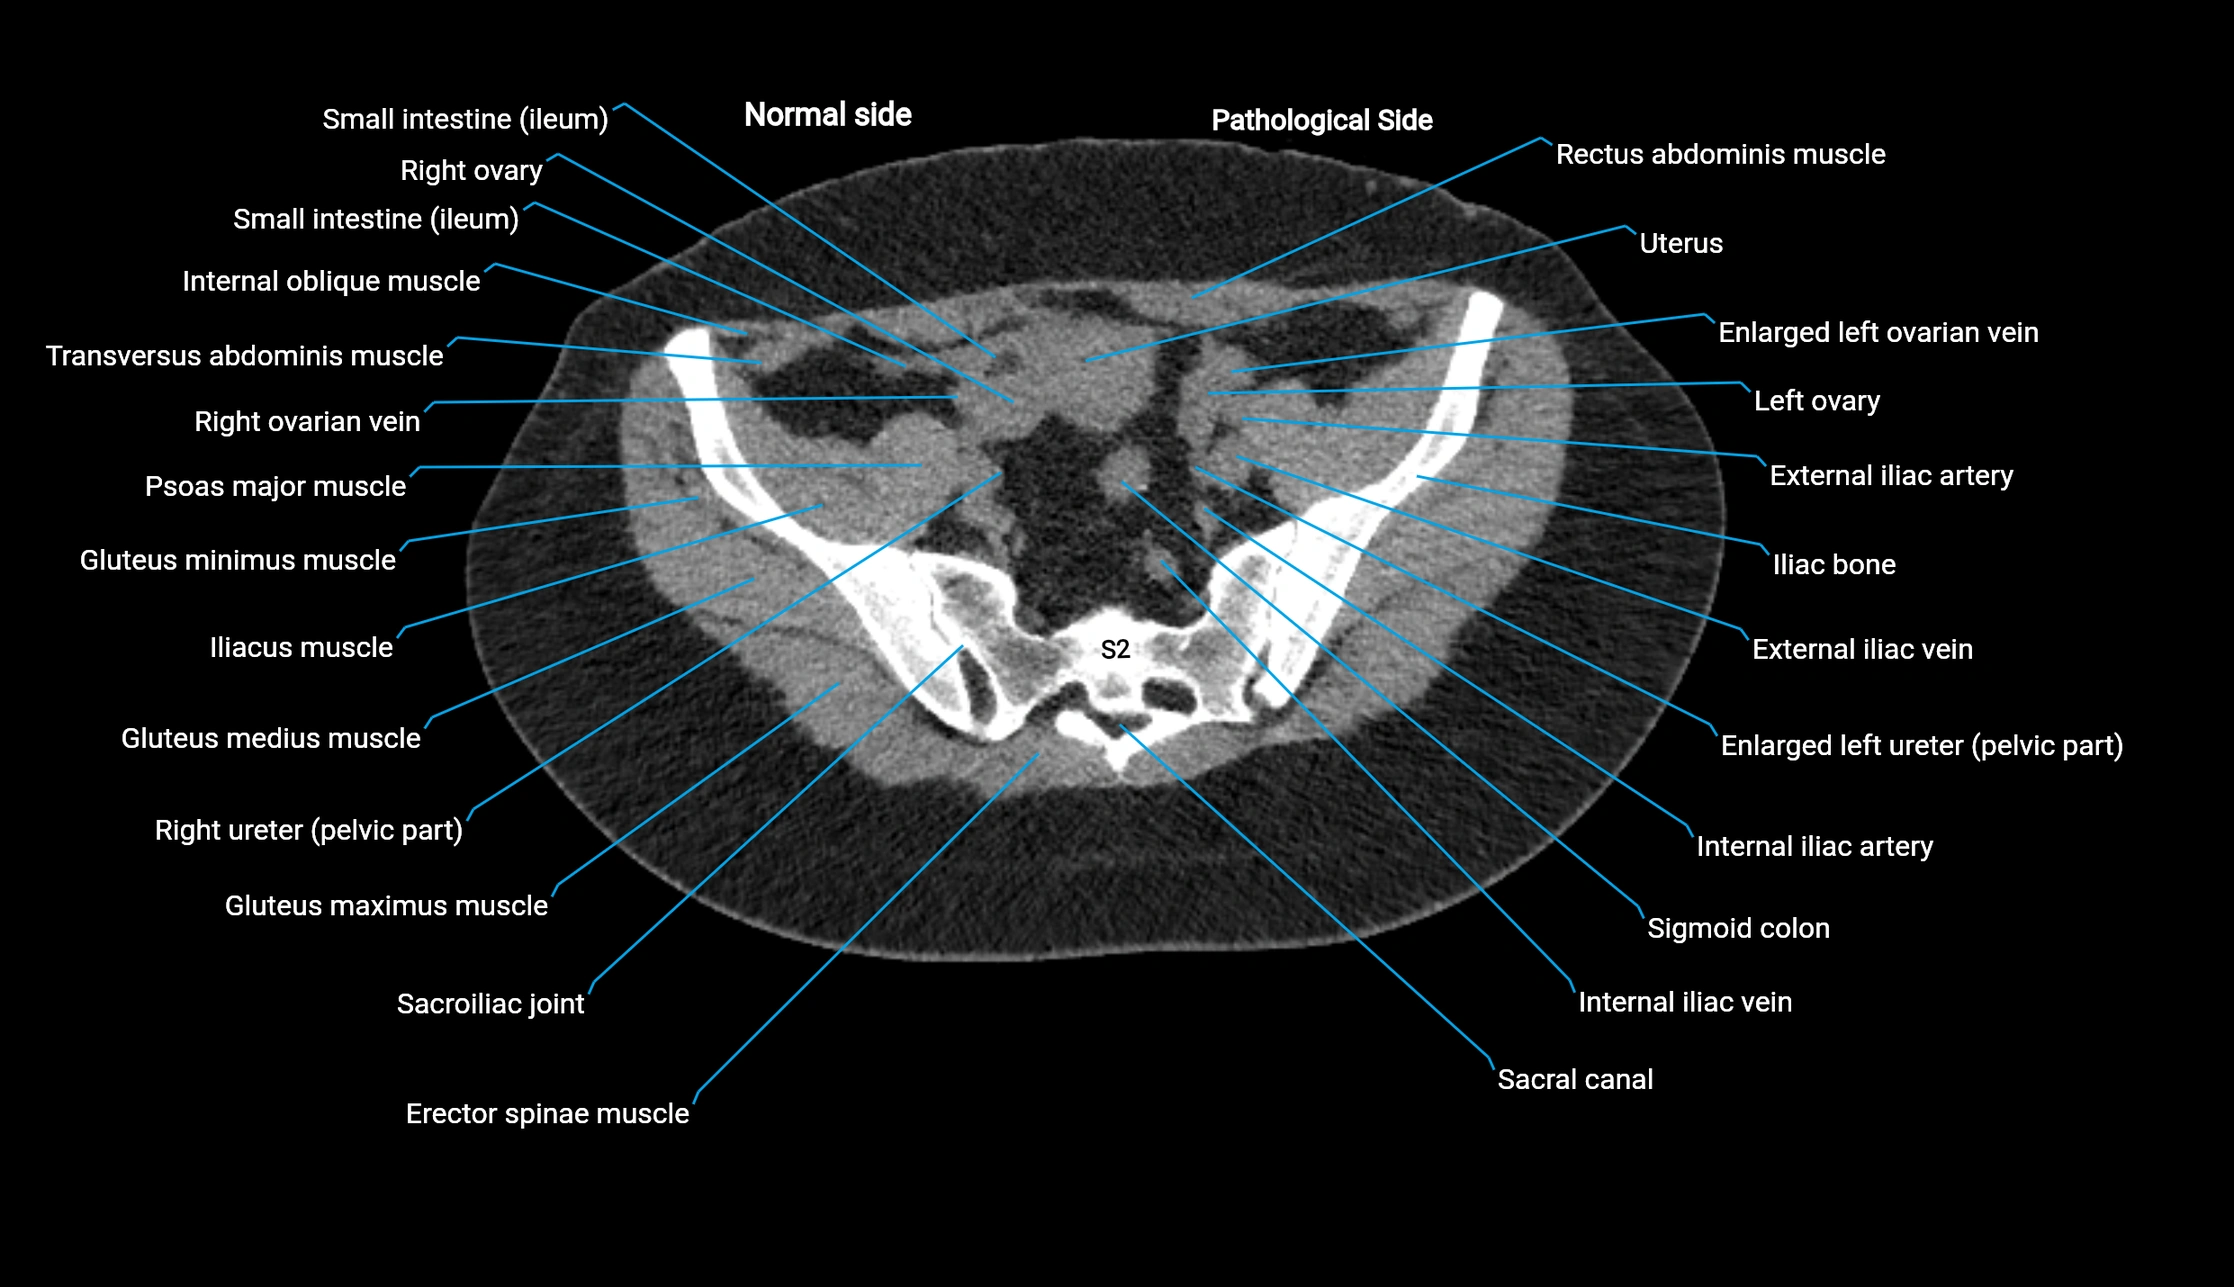

Post-Contrast CT (Contrast-Enhanced CT):

• Portal venous phase:

• Anterior right portal branch enhances intensely and homogeneously

• Clearly separates from posterior branch

• Branching pattern to segments V and VIII sharply defined

• Arterial phase:

• Slight enhancement but less conspicuous than in portal phase

• Coronal and sagittal reconstructions:

• Optimal visualization of segmental bifurcation

• Used for preoperative liver mapping

• CT liver segmentation:

• RAPV acts as the principal boundary landmark for dividing anterior vs. posterior right hepatic segments